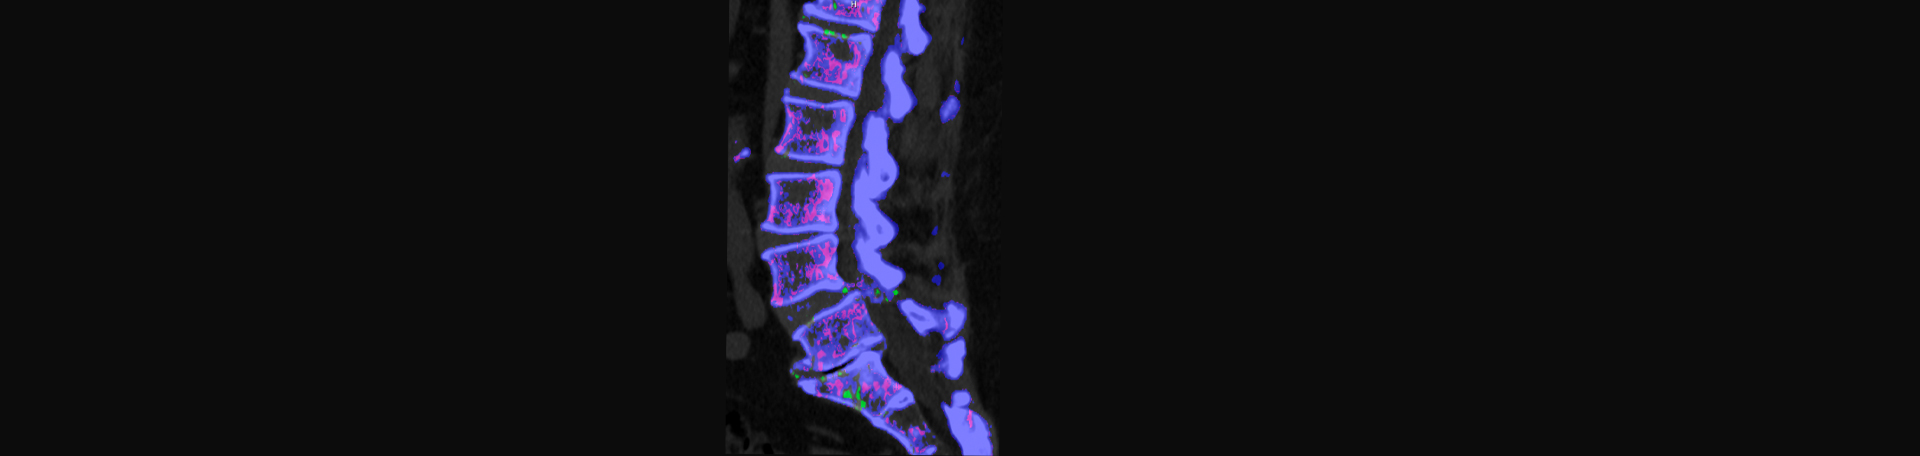

Researchers have investigated a variety of ways to safely and accurately diagnose gout in people who have never experienced gout. They have analyzed studies going back as far as 1945! They found that synovial fluid monosodium urate crystal analysis and imaging were superior to a clinical algorithm of signs and symptoms only for diagnosis and treatment planning. (3) Facet joint disorders, osteoarthritis, synovial cysts, etc., can muddle the diagnostic process for spinal gout. Luckily, dual energy computed tomography (DECT) shows the crystals. However, healthcare providers must be aware that gout is a possible cause to request the proper test. (4) A narrative review of published studies on spinal gout that was completed by two chiropractors concurred. To make better the quality of life of spinal gout sufferers as well as the diagnosis, treatment planning and prevention of surgery, a mix of clinical symptoms, lab tests, and DECT may hold the answer. (2) Aurora Chiropractic Center notes that cases of spinal gout are appearing in the medical literature.